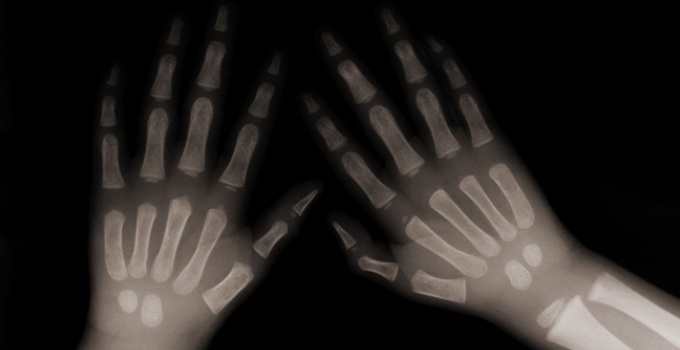

Rhumatologie

Arthrose de la main : de premières recommandations françaises